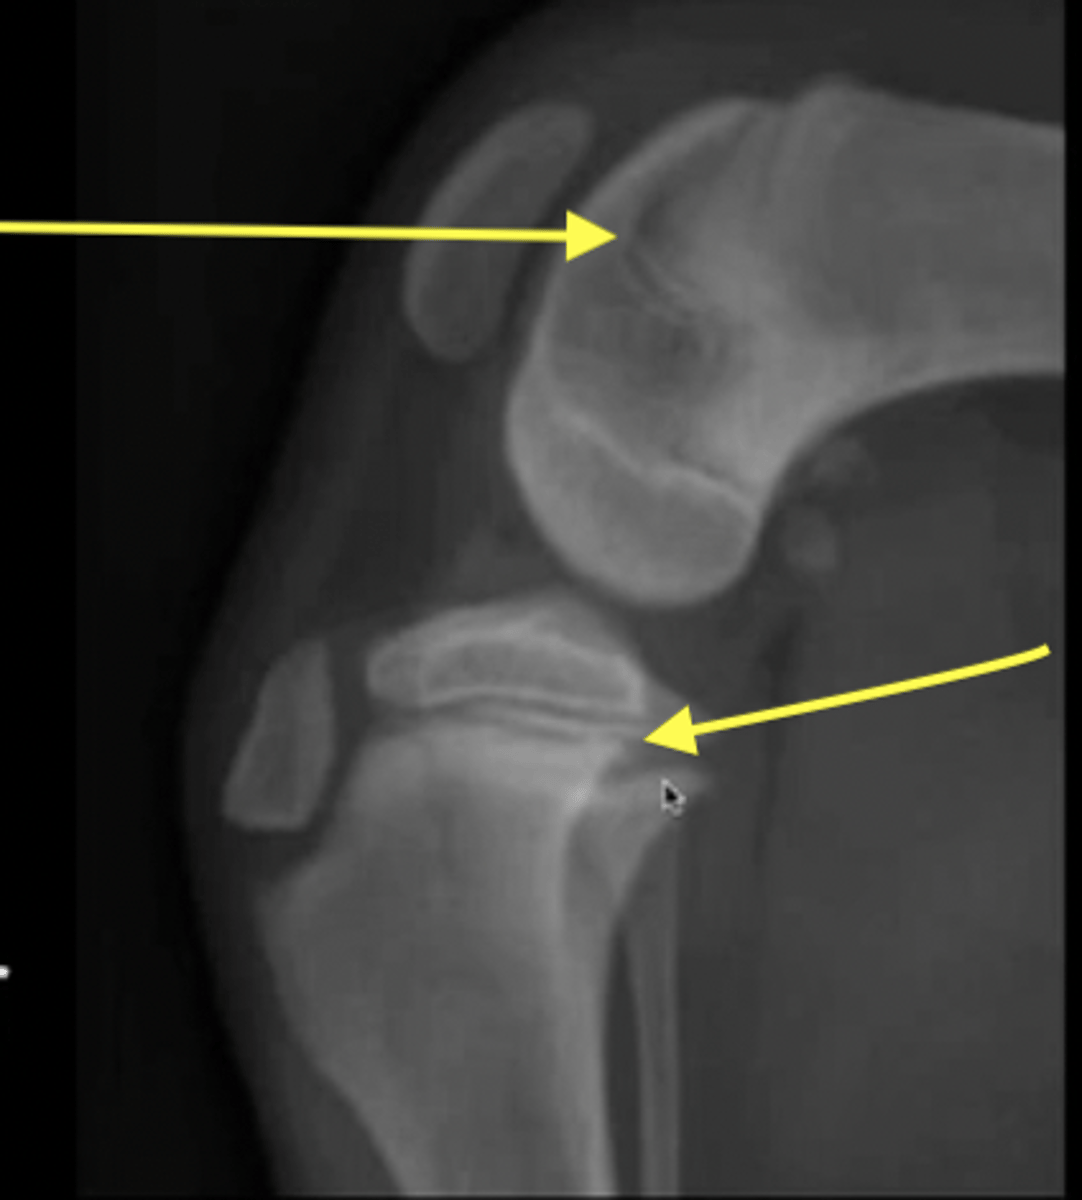

physis

What are the arrows pointing to?